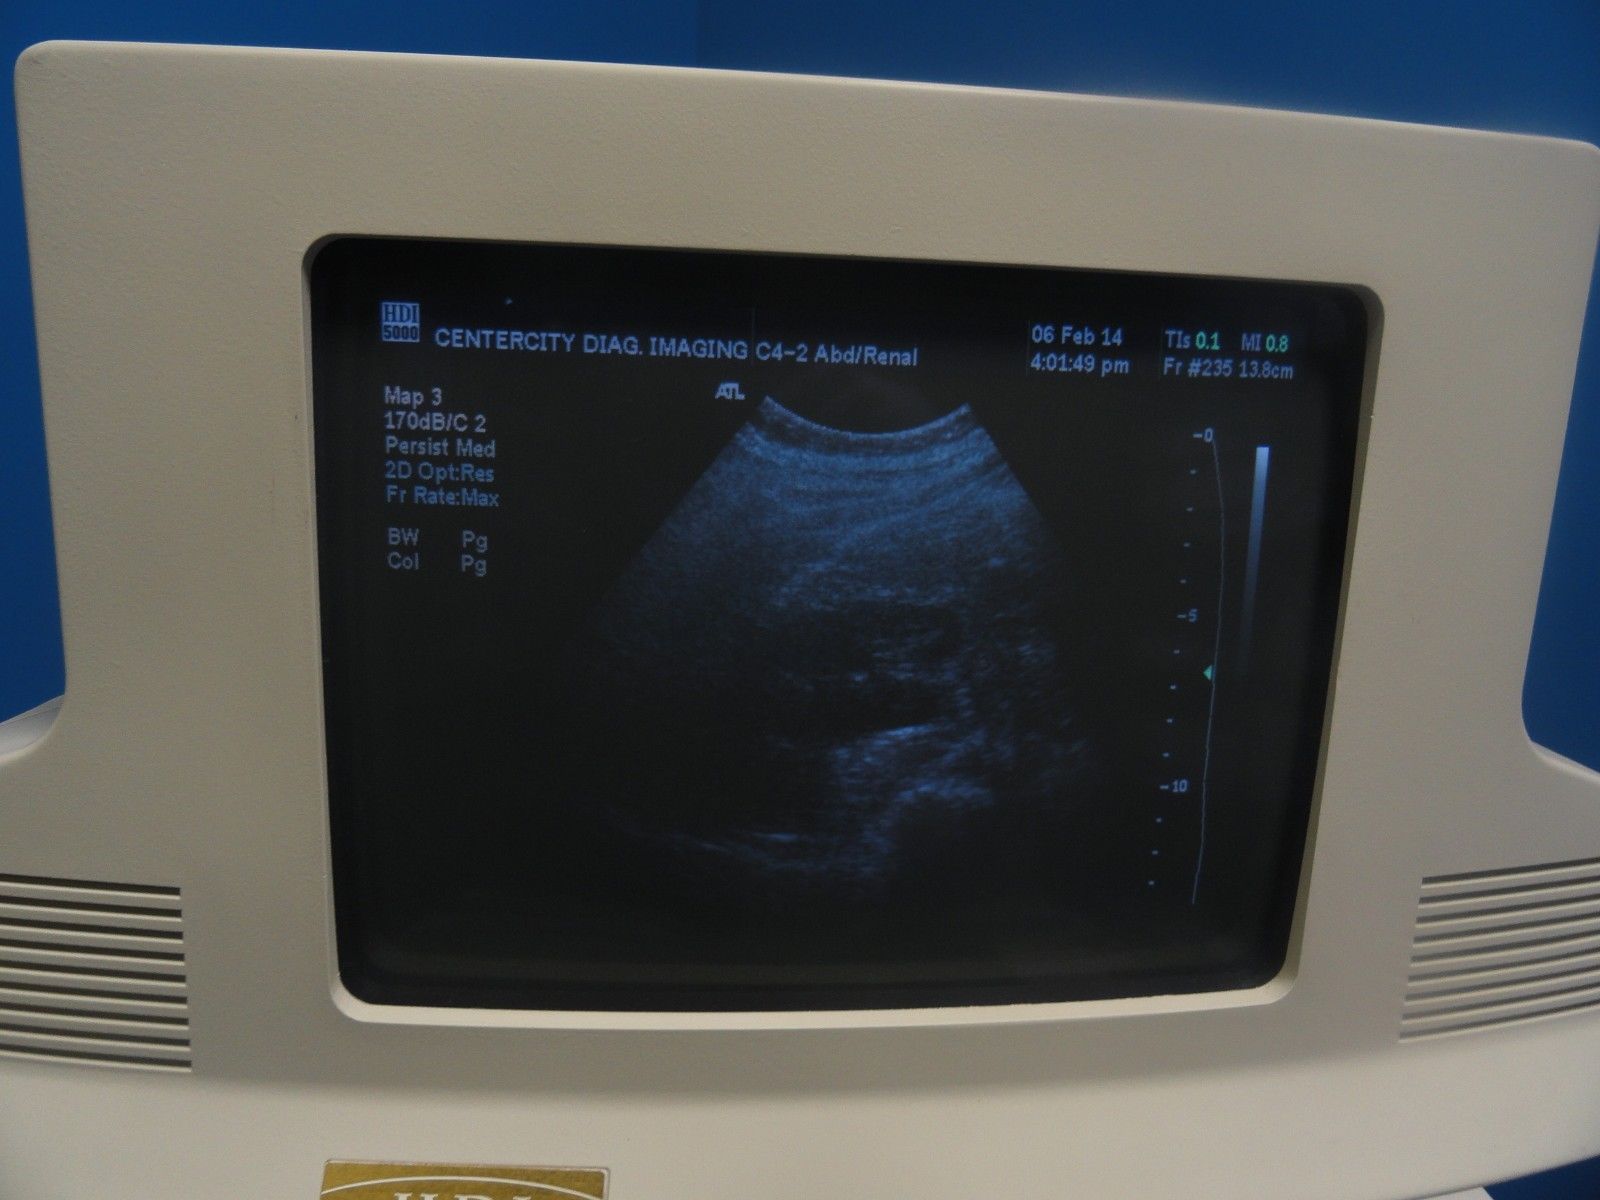

The ATL HDI C4-2 40R Curved Array Broadband Probe (6322) is a versatile ultrasound transducer designed for abdominal and OB/GYN imaging. Featuring a 4-2 MHz frequency range, this curved array probe provides excellent image clarity and depth penetration, making it ideal for imaging both superficial and deeper structures. It is particularly effective for abdominal, obstetric, and gynecological examinations, allowing healthcare professionals to capture clear images of the uterus, ovaries, and other abdominal organs. The broadband capabilities of the C4-2 40R ensure high-resolution images across a wide range of patient types and conditions, while its ergonomic design enhances comfort and ease of use during extended procedures. Compatible with the ATL HDI ultrasound systems, this probe offers seamless integration and optimal performance, helping clinicians make accurate and timely diagnoses. Whether for routine checks or more specialized exams, the ATL HDI C4-2 40R is a reliable, high-performance tool for medical imaging.